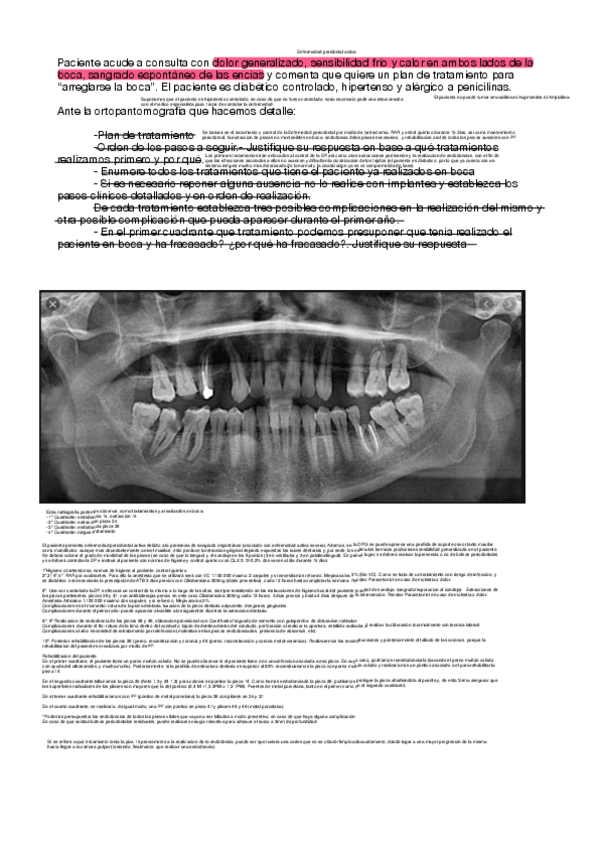

CASOS CLINICOS REPASO

He publicado nuevos ejercicios de 5º CLÍNICA INTEGRADA II: CASOS CLINICOS REPASO